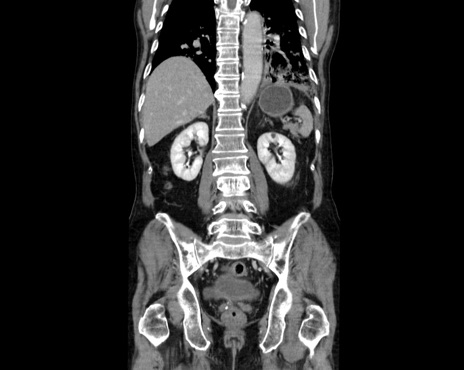

症例26(冠状断像)

【症例】80歳代男性

【主訴】嘔吐

【現病歴】昨晩2回嘔吐あり、今朝になっても嘔吐あり。来院。

【既往歴】胃潰瘍

【身体所見】意識清明、BT 37.6℃、BP 166/95mmHg、HR 100bpm、SpO2 97%、腹部:平坦・軟、腸蠕動音聴取良好、圧痛なし。

【データ】WBC 21900、CRP 1.4